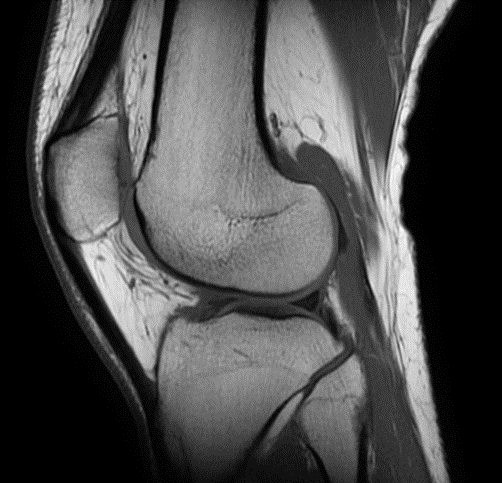

MRI of the Knee

MRI Knee

Course Type Online - Self-paced

A self-paced course detailing MRI of the Knee including Positioning, Geometrics, Anatomy, Sequences and Pathology.